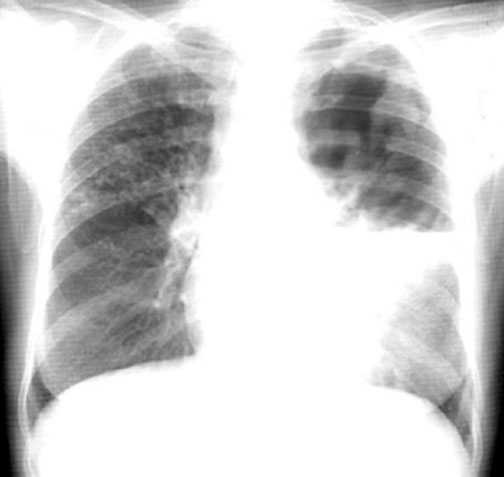

Case 2 Labeled Image What is the differential for multiple cavities?